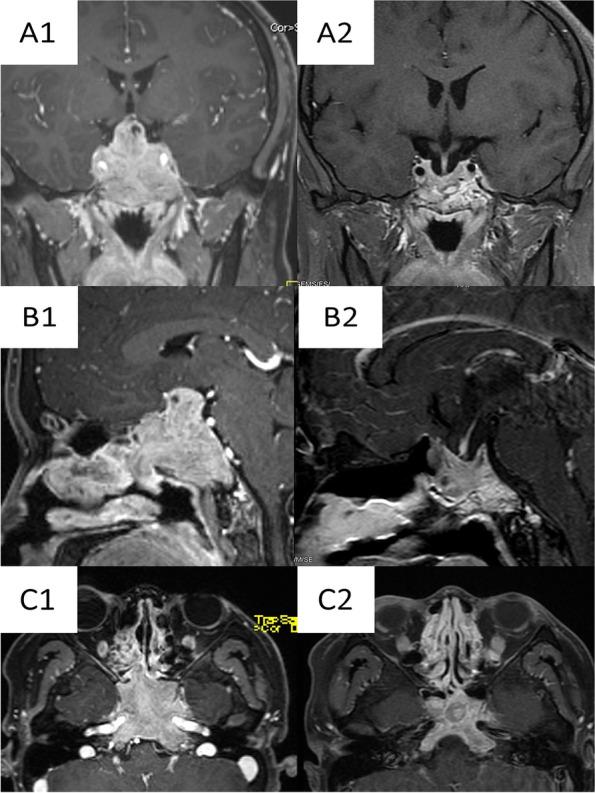

A 24-year-old man with an invasive giant prolactinoma in the nasal cavity and sellar region who presented with nasal bleeding as the initial symptom, misdiagnosed as olfactory neuroblastoma. However, markedly elevated serum prolactin levels (4700 ng/mL), and a 7.8-cm invasive sellar mass confirmed the diagnosis of invasive giant prolactinoma. He was treated with oral bromocriptine. Serum prolactin was reduced to near normal after 6 months of treatment. Follow-up magnetic resonance imaging showed that the sellar lesion had disappeared completely and the skull base lesions were reduced.

一名 24 岁男性,患有鼻腔和蝶鞍区侵袭性巨大泌乳素瘤,以鼻出血为首发症状,误诊为嗅神经母细胞瘤。然而,明显升高的血清泌乳素水平(4700ng/mL)和 7.8 厘米侵袭性鞍区肿块证实了侵袭性巨大泌乳素瘤的诊断。他接受了口服溴隐亭治疗。治疗 6 个月后,血清泌乳素降至接近正常。随访磁共振成像显示鞍区病变完全消失,颅底病变减少。